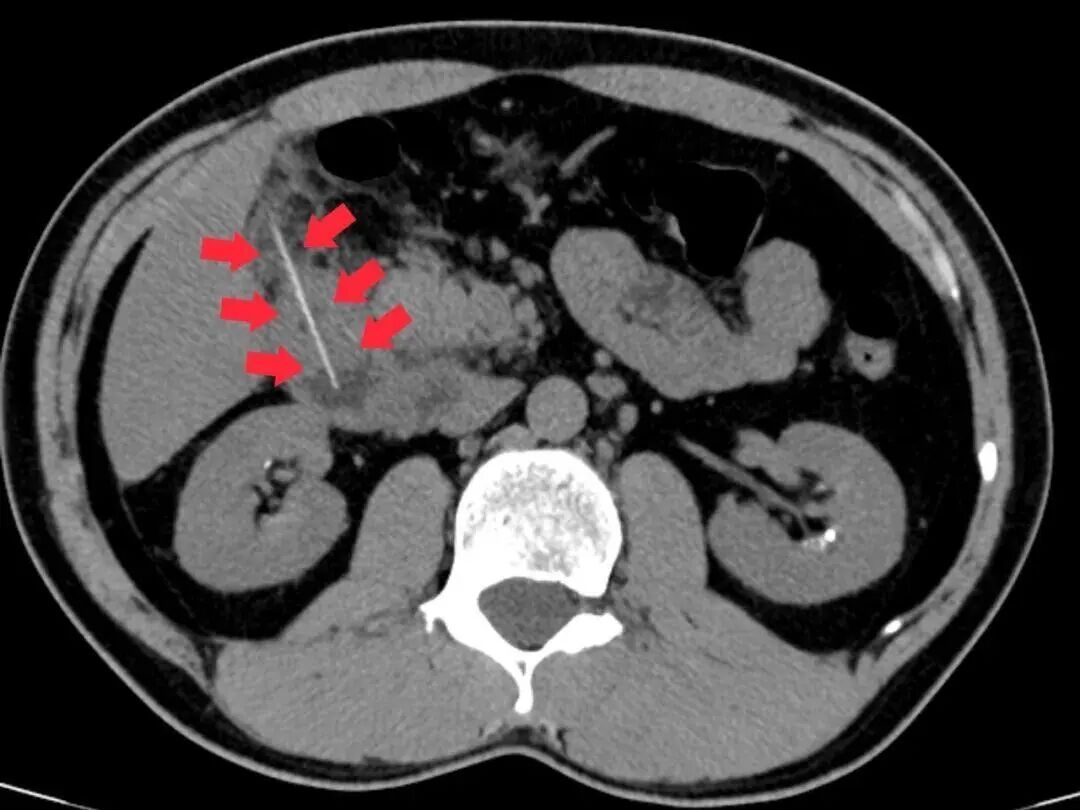

急诊科医生立即为其安排腹部CT检查,结果发现一根牙签滞留于十二指肠降部,且尖端已刺穿肠管壁,引发了局限性腹膜炎。情况危急,若任由发展,可能导致感染扩散、休克甚至危及生命。陈先生随即以“消化道异物并穿孔”被收治入院。

外科团队火速完成术前检查,科主任麦伟锦组织多学科会诊,分析CT影像后发现,穿孔处已形成局部粘连,取出时需控制牵拉力度,决定采取“消化内镜优先、手术兜底” 的双保险方案。医师李伟杰在病床前,用影像直观讲解治疗思路,消除了患者的疑虑。